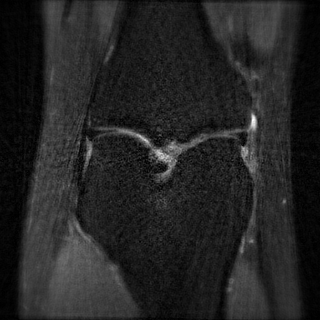

This article presents a novel undersampled magnetic resonance imaging (MRI) technique that leverages the concept of Neural Radiance Field (NeRF). With radial undersampling, the corresponding imaging problem can be reformulated into an image modeling task from sparse-view rendered data; therefore, a high dimensional MR image is obtainable from undersampled $k$-space data by taking advantage of implicit neural representation. A multi-layer perceptron, which is designed to output an image intensity from a spatial coordinate, learns the MR physics-driven rendering relation between given measurement data and desired image. Effective undersampling strategies for high-quality neural representation are investigated. The proposed method serves two benefits: (i) The learning is based fully on single undersampled $k$-space data, not a bunch of measured data and target image sets. It can be used potentially for diagnostic MR imaging, such as fetal MRI, where data acquisition is relatively rare or limited against diversity of clinical images while undersampled reconstruction is highly demanded. (ii) A reconstructed MR image is a scan-specific representation highly adaptive to the given $k$-space measurement. Numerous experiments validate the feasibility and capability of the proposed approach.